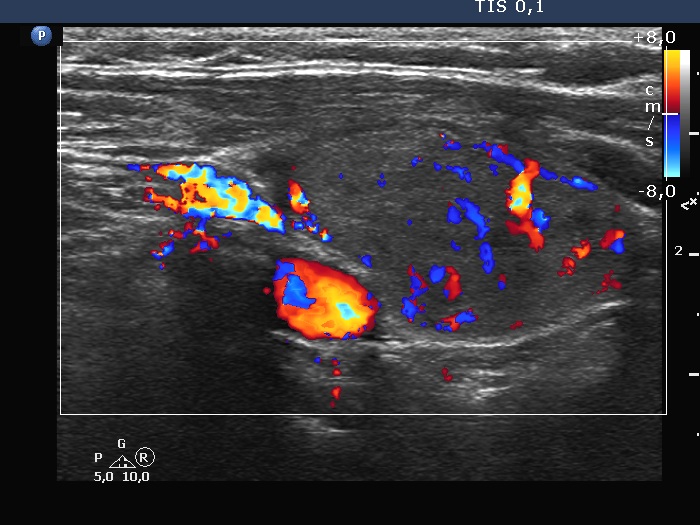

Follow-up investigation 6 years later (ultrasonographic picture 3)

Right lobe, longitudinal scan, color Doppler method. The nodule has increased intranodular vascularity.